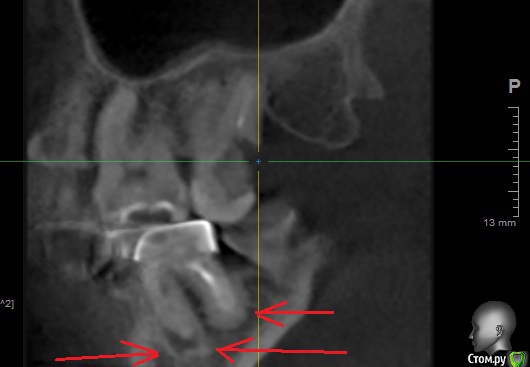

usilitel Опубликовано 10 марта, 2019 Поделиться Опубликовано 10 марта, 2019 На снимке видно что вокруг корней зуба что-то явно ненормальное образовалось (возможно киста?).При этом сам зуб не беспокоит.Были у двух разных врачей - сказали что раз не беспокоит - то ничего делать не надо.А ваше мнение? Ссылка на комментарий